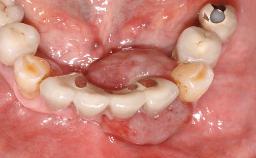

Surgical treatment of a 67-year-old male patient exhibiting an extended edentulous space in the anterior maxilla after the removal of three hopeless incisor teeth.

The video demonstrates implant placement using a surgical stent according to the principle of prosthodontically driven implant placement. The deficient ridge is augmented with locally harvested autologous bone chips, a superficial layer of xenogenic DBBM particles and a resorbable collagen membrane. The surgery is completed with a precise, tension-free primary wound closure.

Case Type Extended Space

Jaw Maxilla

Area Anterior

# of Teeth 4

# of Implants 2